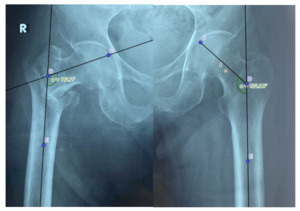

Six months post-surgery, 27 cases had no shortening (77.14%), 7 cases had shortening < 1.5 cm compared to the unaffected side (20%), and 1 case had shortening between 1.5 – 2.5 cm (2.86%).

Recovery of neck-shaft angle immediately post-surgery compared to the unaffected side: 9 cases had their neck-shaft angle restored to that of the unaffected side (25.7%), 5 cases had a larger neck-shaft angle post-surgery (14.3%), and 21 cases had a smaller neck-shaft angle post-surgery, ranging from 1 to 15 degrees smaller than the unaffected side (40%).

Change in neck-shaft angle at the final assessment compared to immediately post-surgery: nearly 70% of cases showed no change in the neck-shaft angle of the femur six months after surgery, while 30% exhibited a decrease (varus deformity), with the majority experiencing a decrease of 1 – 5 degrees (22.86%).